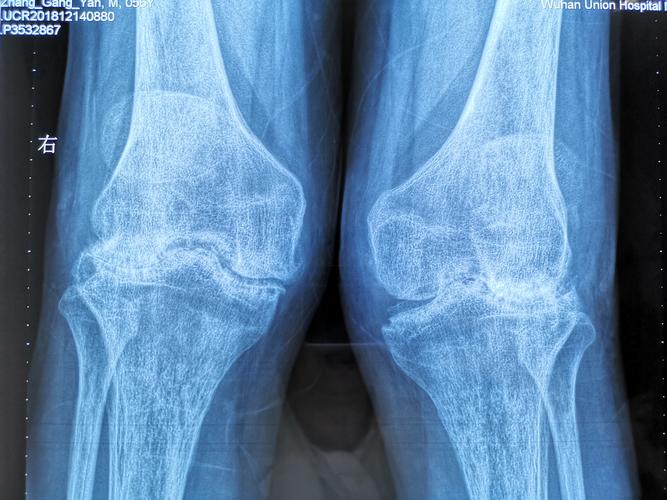

- 关节积液:在膝关节等大关节,可见“脂肪垫征”模糊或消失(髌下脂肪垫因肿胀而密度增高)。

- 骨质疏松:RA早期即可出现,且与关节炎症程度相关,表现为骨小梁稀疏、骨皮质变薄,以关节周围,尤其是承重区(如股骨近端)最为明显,这是由于炎症因子导致破骨细胞活性增强所致。

中期(关节间隙狭窄和骨侵蚀)

- 关节间隙狭窄:这是RA的特征性改变之一,由于滑膜血管翳(pannus,一种增生的、具有侵袭性的炎性组织)覆盖并侵蚀关节软骨,导致关节间隙进行性、对称性变窄,通常从关节的边缘开始,逐渐累及整个关节间隙。

- 骨侵蚀:这是RA最具特征性的影像学标志,也是诊断RA的关键标准之一,侵蚀灶的特点是:

- 位置:通常出现在关节边缘(非承重面),特别是肌腱、韧带和关节囊的附着点附近。

- 形态:表现为边缘清晰、锐利的骨质缺损,可呈“虫噬状”或“穿凿样”。

- 好发部位:手指的近端指间关节和掌指关节,以及腕关节(尤其是桡尺远侧关节和腕骨间关节)是最常受累的部位,足部的跖趾关节也常见。

晚期(关节畸形和强直)

- 关节畸形:由于关节结构和韧带的破坏,导致关节半脱位和畸形,典型畸形包括:

- 尺侧偏斜:手指向小指侧偏斜。

- 天鹅颈畸形:手指的近端指间关节过伸,远端指间关节屈曲。

- 纽扣花畸形:手指的近端指间关节屈曲,远端指间关节过伸。

- 关节强直:晚期,严重的破坏和修复可导致纤维性或骨性强直,使关节活动完全丧失。

- 病理性脱位/半脱位:如指间关节半脱位。